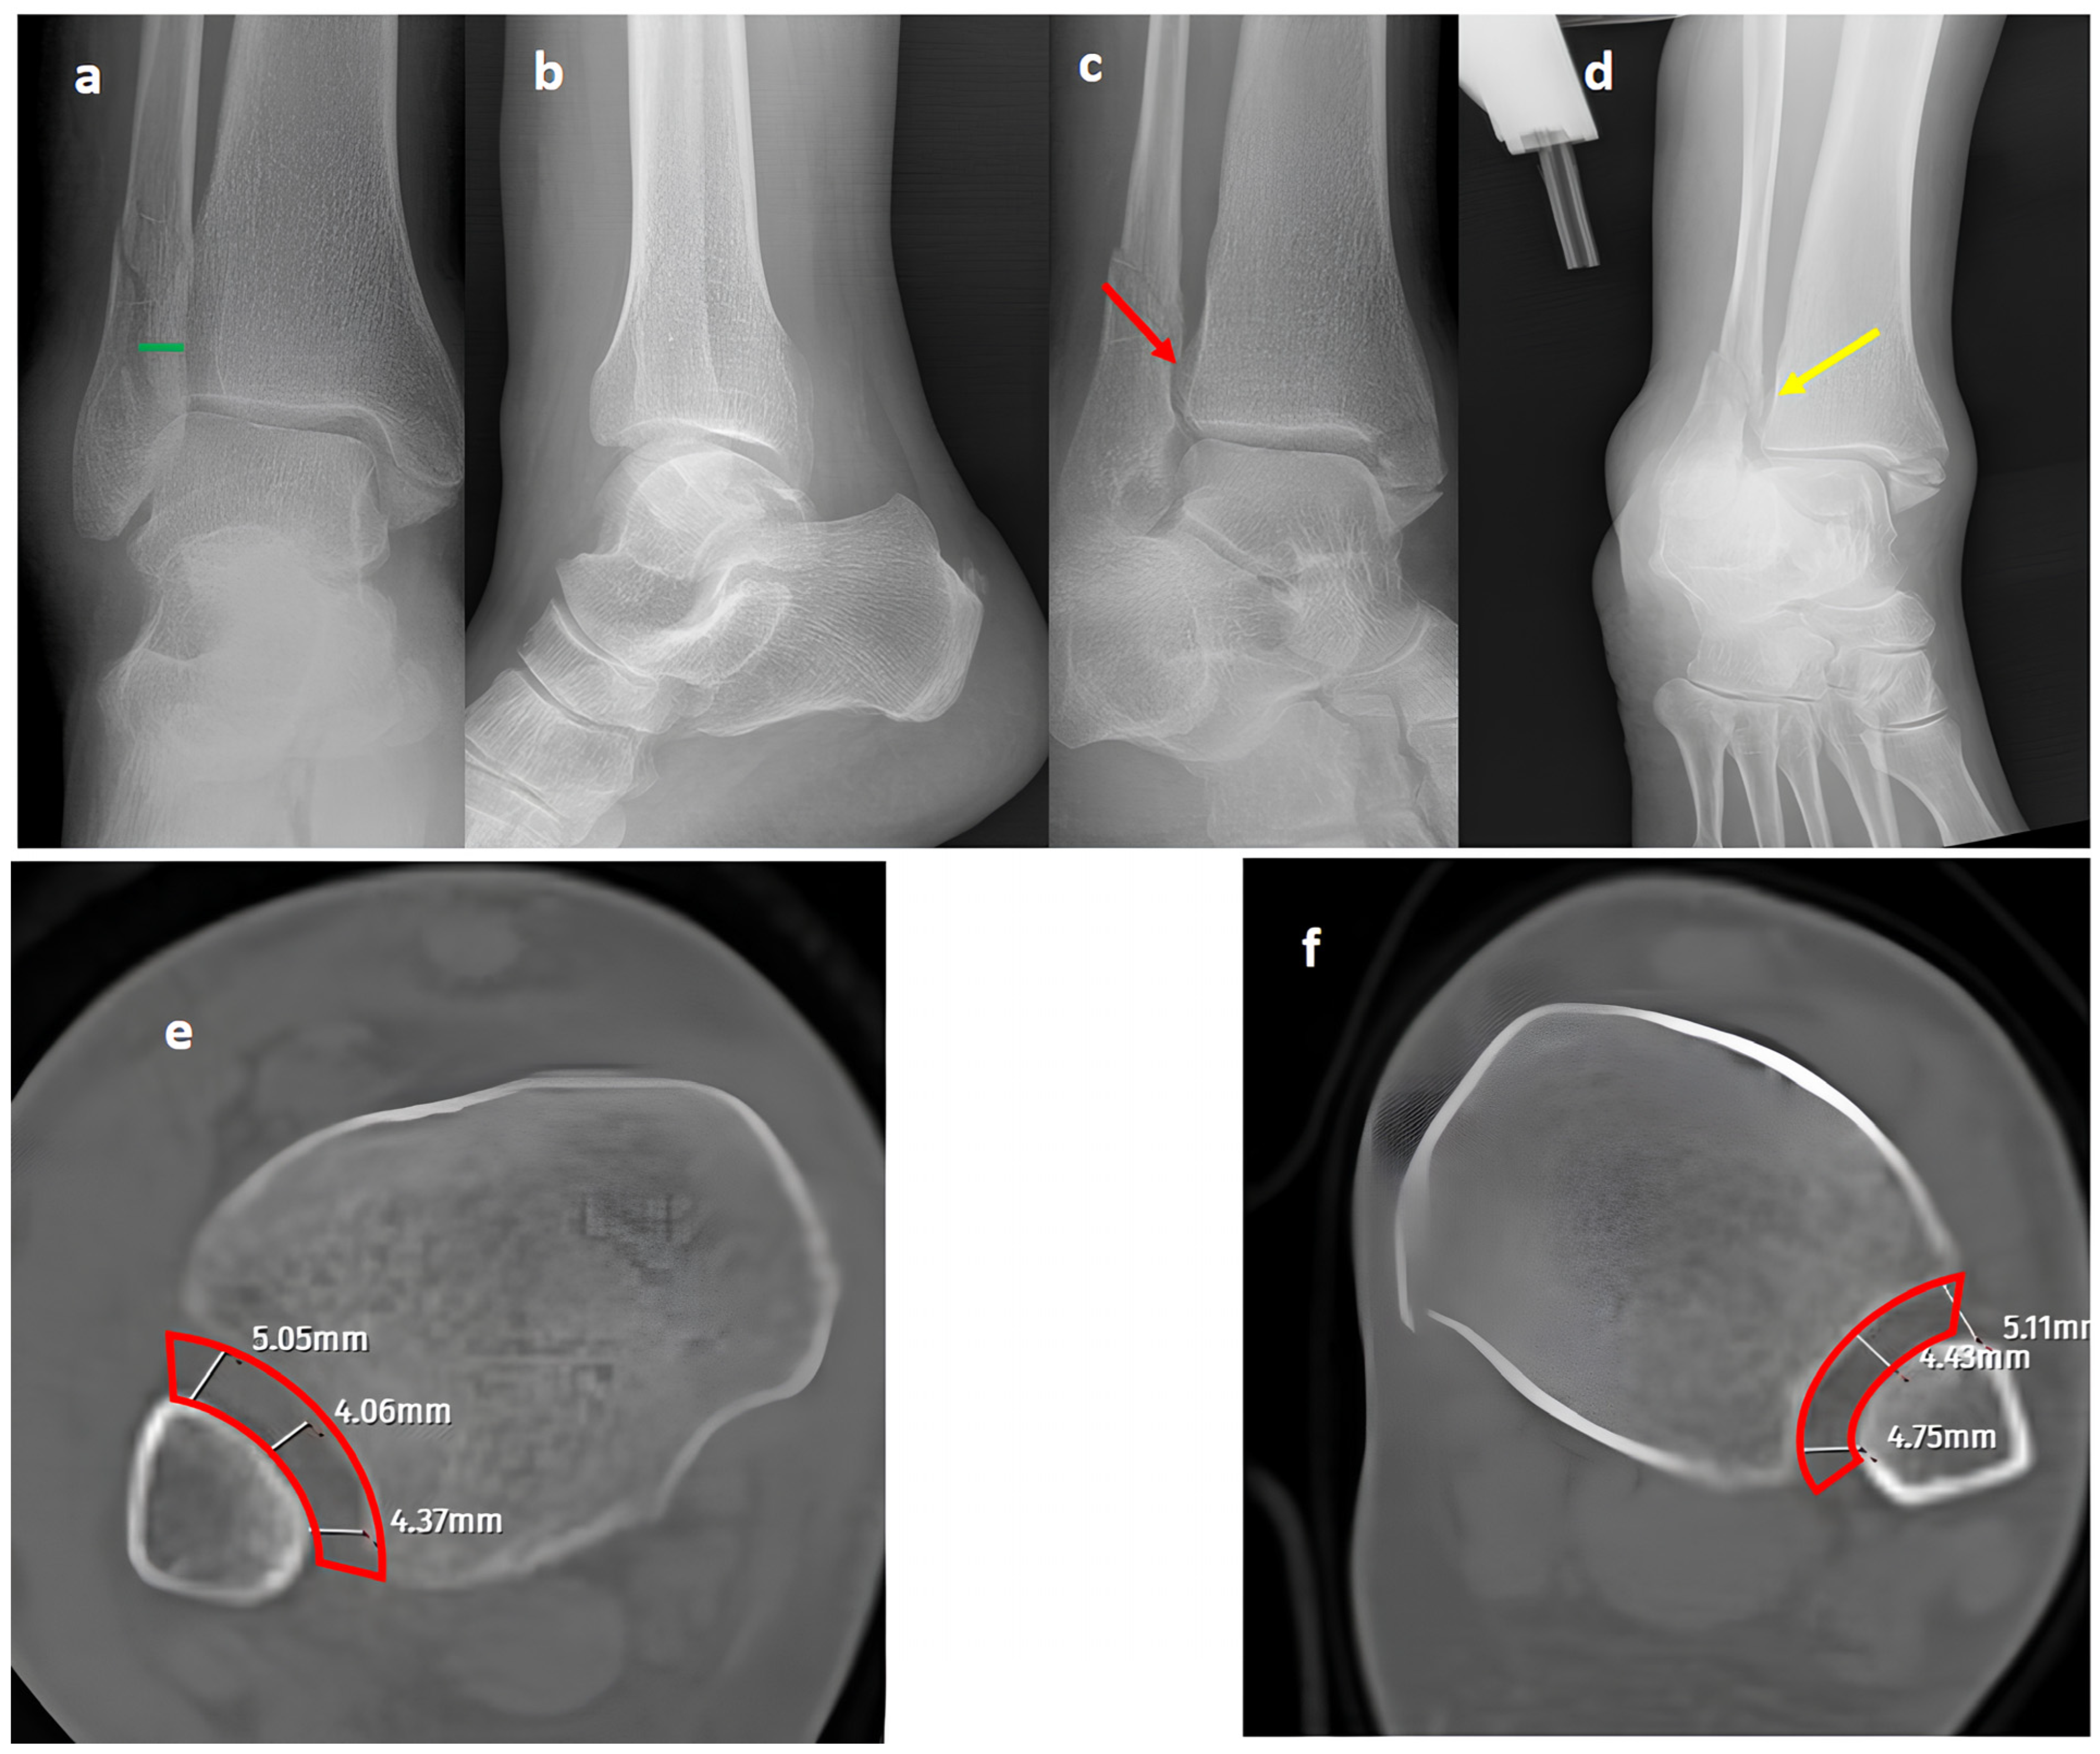

Figure 1. A trimalleolar right ankle fracture. (a,b) Standard AP and lateral views showing a bimalleolar fracture with a normal distal tibiofibular overlap (green line). (c) A mortise view showing an open distal tibiofibular distance (red arrow) indicating syndesmosis injury. (d) A GAASA view showing lateral displacement of the talus with a shift in the medial malleolus and distal fragment of the fibular segment. However, the proximal segment of the fibula is in place, indicating that the proximal syndesmosis is intact (yellow arrow). Axial CT images of the injured right ankle (e) and the uninjured left ankle (f) show measurement of the tibiofibular space (red block bow), which appears similar and within normal ranges, indicating an intact syndesmosis.

In our series, 19 of 36 SER type II and IV cases did not involve syndesmotic injury (Figure 1), which is consistent with the idea that medial and lateral injuries must be carefully assessed before surgical stabilization. These findings highlight that GAASA imaging is particularly reliable in PER injuries, where all medial and lateral structures are disrupted and the fibula is extensively fractured. In such cases, gravitational force causes the talus to exert downward pressure on the distal fibular fragment, producing clear widening of the medial clear space and distal tibiofibular joint [28]. Maisonneuve injuries, not classified by the Lauge-Hansen system, are inherently unstable and require surgical syndesmosis stabilization [29]. In our study, three cases had clear distal tibiofibular widening without pathological medial clear space widening (Figure 2). This contrasts with the cadaveric study by Krahnebühl et al., which reported that stress radiographs are reliable only when deltoid and syndesmotic injuries coexist, but are ineffective for isolated syndesmosis injuries [5]. Our findings suggest that even when the medial malleolus and deltoid ligament remain intact, gravitational force alone can cause lateral fibular displacement, resulting in decreased tibiofibular overlap.